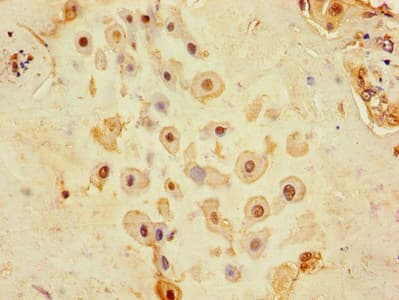

Anti-CD9 antibody(ab223052)

Rabbit Polyclonal CD9 antibody. Suitable for WB, IHC-P and reacts with Rat, Mouse, Human samples. Cited in 60 publications. Immunogen corresponding to Recombinant Fragment Protein within Human CD9 antigen aa 100-200.

Applications IHC-P, WB

Species Reactivity Human, Mouse, Rat